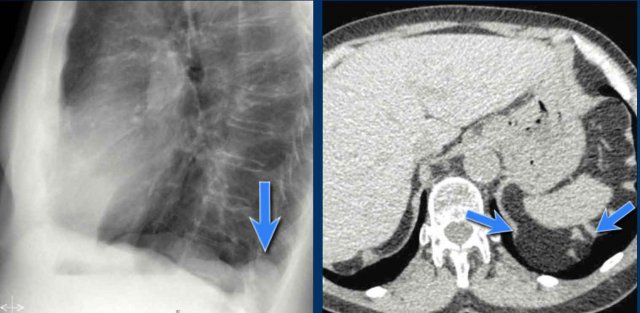

CT correlation

The explanation for the cardiac incisura is seen on this CT-image.

At the level of the inferior heart, the right lower lobe (blue arrow) is often seen extending more anteriorly than the left lower lobe (red arrow) , explaining the asymmetry of the cardiac incisura.